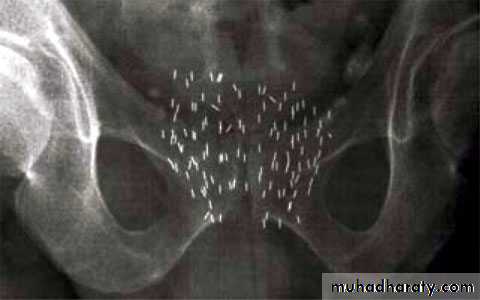

213. Radiation therapy

external beam therapybrachytherapy